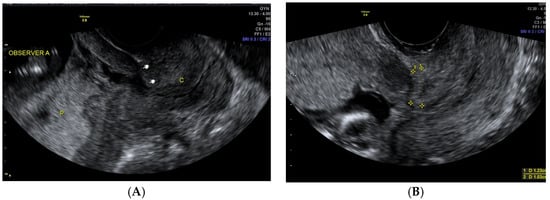

The placental site was evaluated with a transabdominal probe. The women were asked to have their bladder filled normally during the ultrasound examination. In cases where the transabdominal ultrasound indicated a low-lying placenta, a transvaginal scan was applied. Placental locations were recorded prospectively using high-anterior, high-posterior, low-anterior, and low-posterior subgroups. In cases when the placenta was “left- or right-anterior”, it was classified as “anterior”, and similarly, “right- or left-posterior” was classified as only “posterior” (Figure 2A,B).

Figure 2. (A) TVS at the first trimester of pregnancy, posterior-low placenta and CS scar niche. P, placenta; C, cervix. (B) TVS at the first trimester of pregnancy, visible CS scar, non-forming niche, anterior-low placenta.